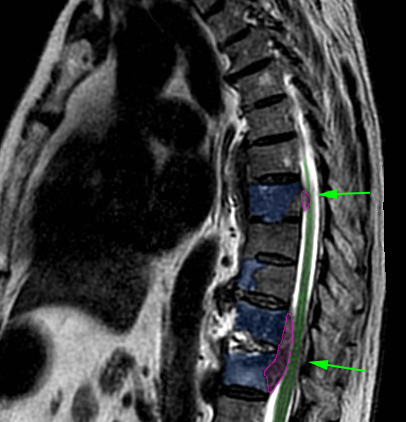

Πολλαπλές μεταστάσεις σπονδυλικής στήλης τόσο στα σώματα των σπονδύλων όσο και εντός του σπονδυλικού σωλήνα (φούξια) με πίεση στο νωτιαίο μυελό (πράσινα βέλη). |